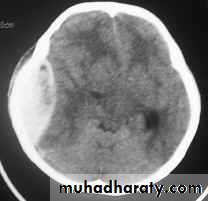

c. Intracerebral Haematoma

This is the least common of traumatic haematoma.

They are due to areas of traumatic contusion coalescing into a contusional haematoma.

Disrupted cerebral tissue release thromboplastins that potentiate haemorrhage.

CT scan: appear as hyperdence lesions with associated mass effect and midline shift.

Large intracerebral haematomas should be evacuated unless the patient’s neurological state is improving.

Small inracerebral haematomas may not require removal, but be aware that they can expand.